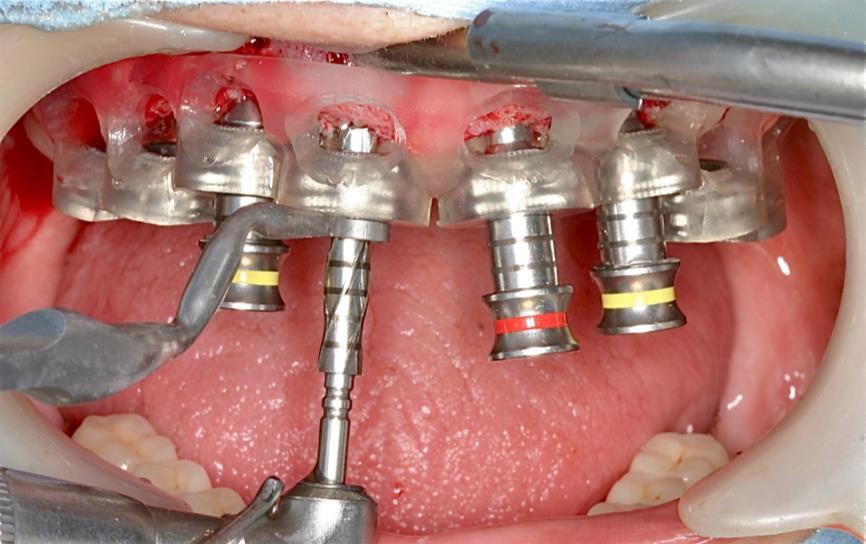

術後3ヶ月 印象時の軟組織の状態

ガイドサージェリーのスターティングに また形成にもガイドの動揺を最小限にすることができる。ひいては所定の位置に近い埋入が可能になる

傾斜埋入の際の形成にもドリルのずれが無く、ガイドを揺さぶることも起こりにくい